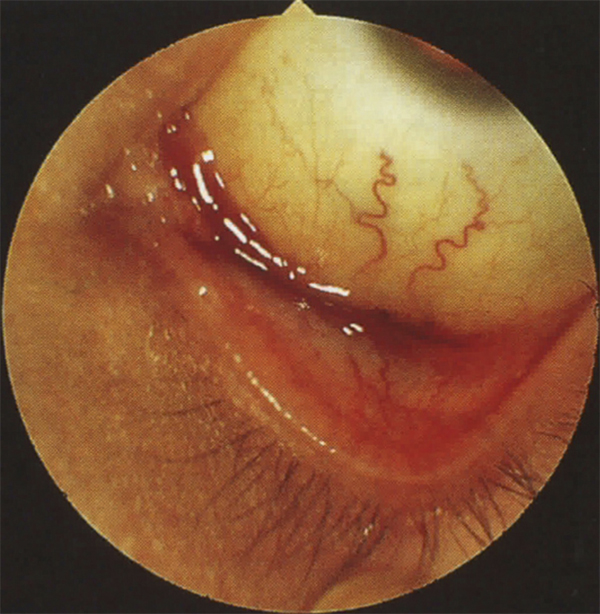

Fig. 6-11 Trachome au stade cicatriciel : opacité cornéenne supérieure avec néovascularisation cornéenne.

complications cornéennes : kératites ponctuées superficielles (en général dans la partie supérieure de la cornée), infiltration stromale antérieure, néovascularisation superficielle (pannus) et ulcères trachomateux entraînant des cicatrices astigmatogènes et opaques (fig. 6-11) ;